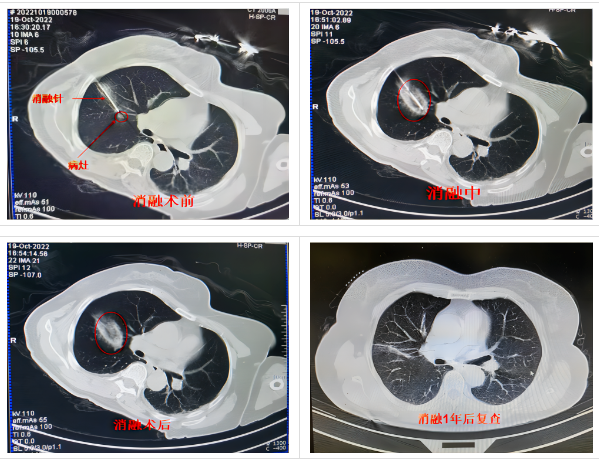

通过将一根1.7-3毫米的中空钢针,穿刺进入肿瘤,先注入氩气,迅速降温至-160摄氏度,冰冻肿瘤数分钟,再注入氦气,快速升温至20-30摄氏度,让肿瘤细胞在短时间内经历“冰火两重天”而破裂损毁。或许这听起来有点匪夷所思!这就是氩氦刀冷冻消融技术。

微创治疗。在局部麻醉下,通过超声、CT等仪器引导或者直视下操作,使用粗细如牙签的冷冻探针穿刺至肿瘤组织,因手术范围仅局限于病灶,所以临近正常组织损伤较小,手术并发症少、创伤小、痛苦小、恢复快。

肿瘤在进行冷冻消融后,冷冻区域的“病灶”可能会显示扩大,这是正常的病理变化,只要术后按期随访观察,一般情况下,半年至一年内会吸收完全。